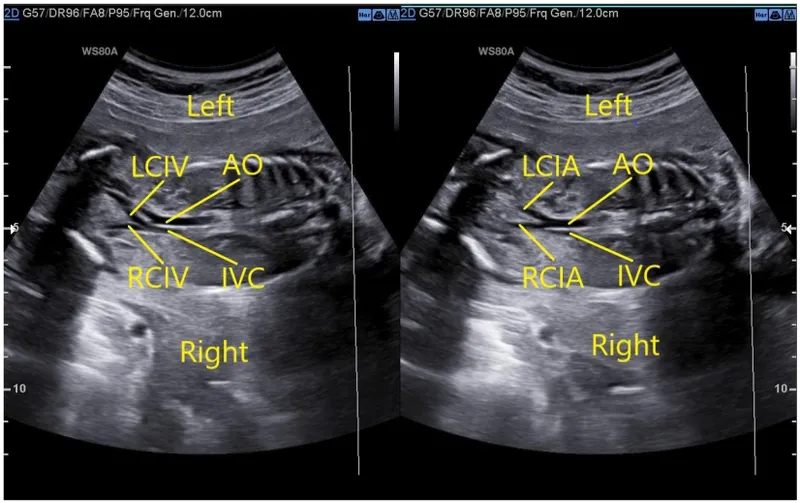

- Aortic Bifurcation: Divides into common iliac arteries at L4 (navel level).

- L4: Bifurcation of the abdominal aorta.

- The aortic bifurcation into common iliac arteries is a reliable landmark at the L4 level.